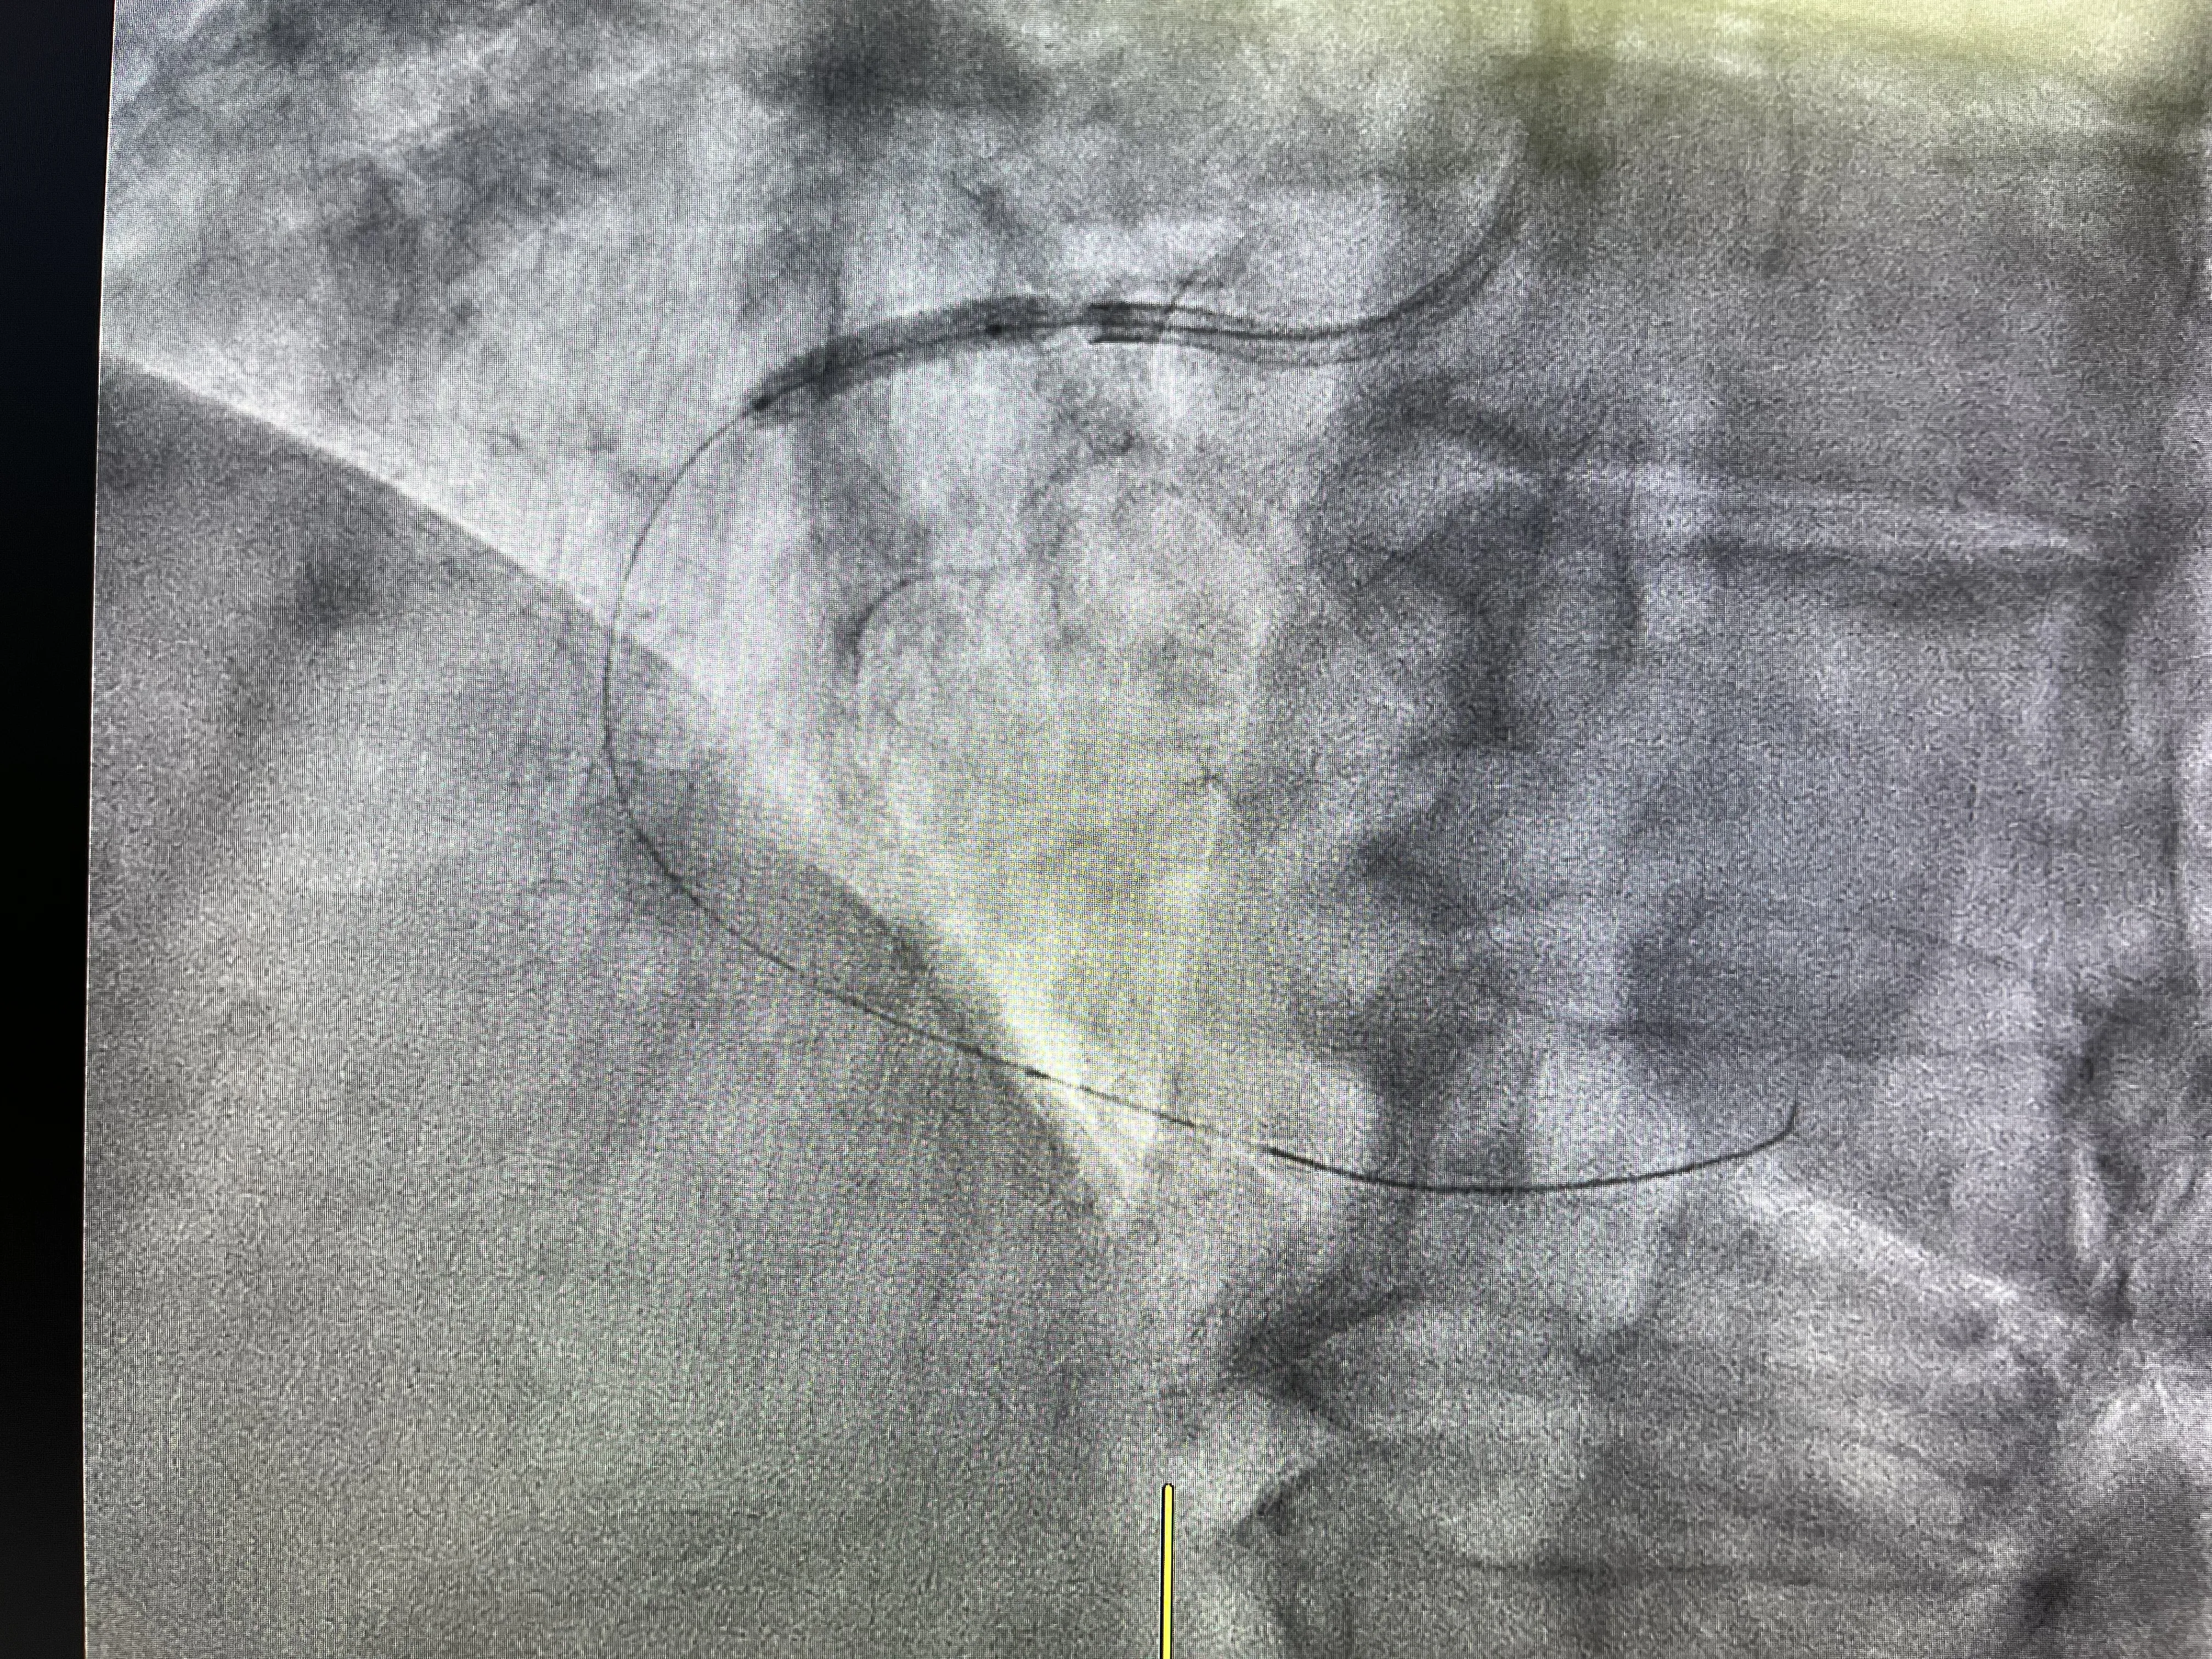

Tras el estudio diagnóstico del lado izquierdo, el siguiente paso fue seleccionar un catéter guía adecuado para la coronaria derecha. A diferencia del catéter diagnóstico, el catéter guía está diseñado no solo para opacificar el vaso, sino también para permitir el paso de material terapéutico como guías, balones y stents. Esta elección es fundamental, porque de ella depende la estabilidad del sistema durante todo el procedimiento de intervención. Un buen apoyo del catéter guía facilita tanto el cruce de la lesión como las maniobras posteriores de dilatación e implante.

En este caso real, el catéter guía se utilizó específicamente con la intención de tratar la arteria coronaria derecha una vez confirmada su obstrucción. Su función principal fue proporcionar un acceso estable y seguro al segmento ocluido, permitiendo trabajar con precisión dentro de la lesión. Además, el catéter guía asegura una adecuada inyección de contraste para valorar en todo momento la posición de la guía y el resultado de cada paso. De este modo, se convierte en la herramienta central sobre la que se articula toda la intervención en la coronaria derecha.